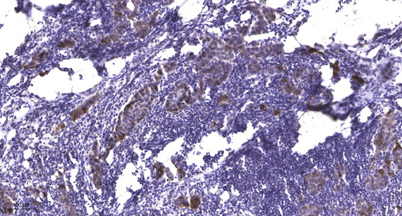

Applications IHC

Recomended Dilution IHC-p 1:50-300